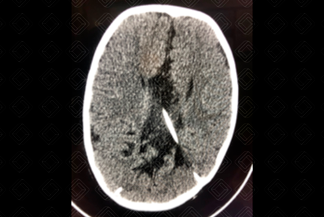

Descrição das imagens: Tomografia computadorizada do plano axial, exibindo a fossa posterior pequena e interdigitação da foice cerebral. Achados compatíveis com malformação de Chiari tipo 2. Observa-se ainda a presença de cateter de derivação ventricular na região parietal posterior esquerda.

• Tomografia computadorizada do crânio: Fossa posterior obliterada (pequena), incisura do tentório alargada, mesencéfalo em bico e deslocamento inferior do vérmis cerebelar;